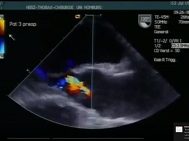

Direct surgical transcatheter heart valve implantation in a calcified mitral valve

Transapical valve-in-ring mitral valve implantation through anterior mitral valve leaflet